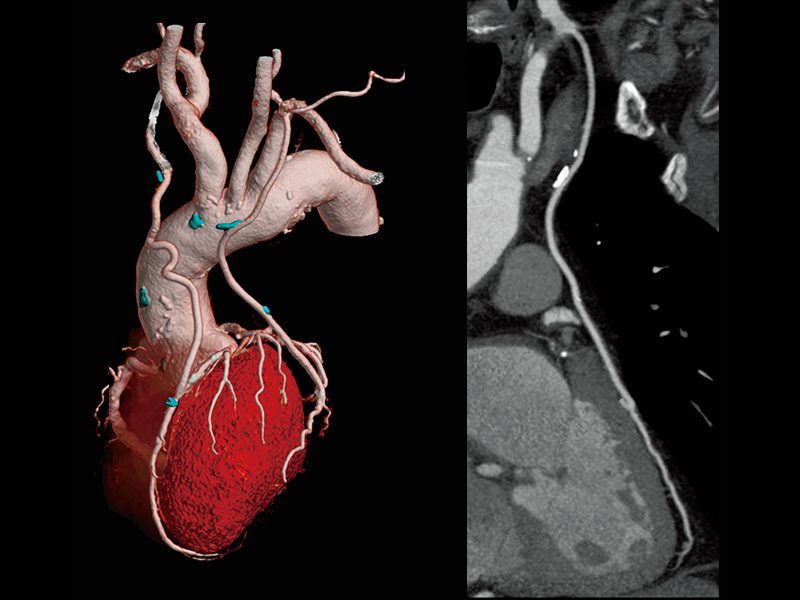

Follow-up after CABG

Follow-up after LAD stenting

High-speed imaging(180 mm/sec)